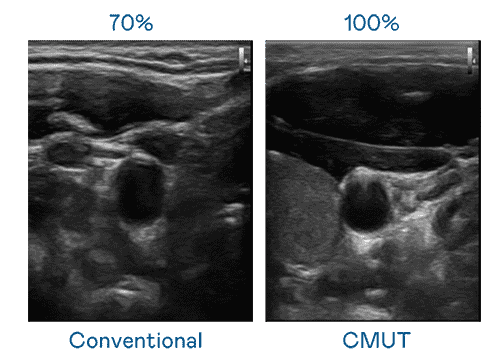

CMUT 技术是一种用电容式微机电元件来产生超音波讯号的技术。。与传统 PZT 压电式技术相比,,,CMUT 频宽增加 30%,,,更宽频的超音波讯号让影像解析度大幅提升,,,是实现高影像品质医疗超音波扫描、、促进精准医疗发展的关键技术。。

大频宽带来超清晰影像

超音波影像的解析度高低,,首先取决于探头能发出的讯号频宽。。。2121非凡 CMUT 可提供高清晰的超音波讯号,,提供高频宽、、高灵敏度、、、、影像纹理细节更高的超音波影像,,协助医护人员缩短影像判读时间及利用精准的医疗影像进行诊断。。。。